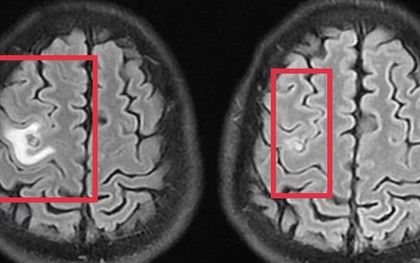

Co giật do sán não suýt nhầm lẫn với u não

Tổn thương não do sán khiến bệnh nhân co giật, đau đầu nhẹ - triệu chứng mờ nhạt nhưng dễ bị bỏ sót.